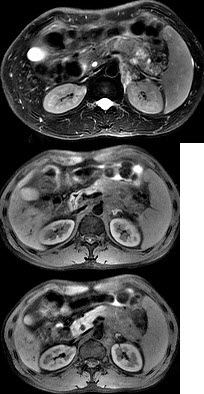

男45岁、腹部胀痛不适、胃纳减退、体重减轻、中腹部可触肿块,影像检查如图,应诊断为( )

A:急性胰腺炎

B:慢性胰腺炎

C:胰腺体尾部癌

D:胰岛细胞瘤

E:腹膜后淋巴结结核